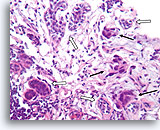

Ductaal carcinoom in situ, Borst FNA, Celblok.

Vergeleken met de onregelmatige, infiltratieve groepen zijn in deze afbeelding de vier profielen van maligne ductale cellen alle omgeven door een glad, dicht, helderroze collageen basaalmembraan. Merk op hoe de fibroblasten net buiten het basaalmembraan zijn georganiseerd met hun lange as parallel aan het basaalmembraan (pijlen). Net als bij kernbiopten van de borst sluit de afwezigheid van invasiviteit in dit ene plaatje geen invasiviteit uit in andere gebieden.

40X

Ductaal carcinoom in situ, Borst FNA, Celblok.

Vergeleken met de onregelmatige, infiltratieve groepen zijn in deze afbeelding de vier profielen van maligne ductale cellen alle omgeven door een glad, dicht, helderroze collageen basaalmembraan. Merk op hoe de fibroblasten net buiten het basaalmembraan zijn georganiseerd met hun lange as parallel aan het basaalmembraan (pijlen). Net als bij kernbiopten van de borst sluit de afwezigheid van invasiviteit in dit ene plaatje geen invasiviteit uit in andere gebieden.

40X